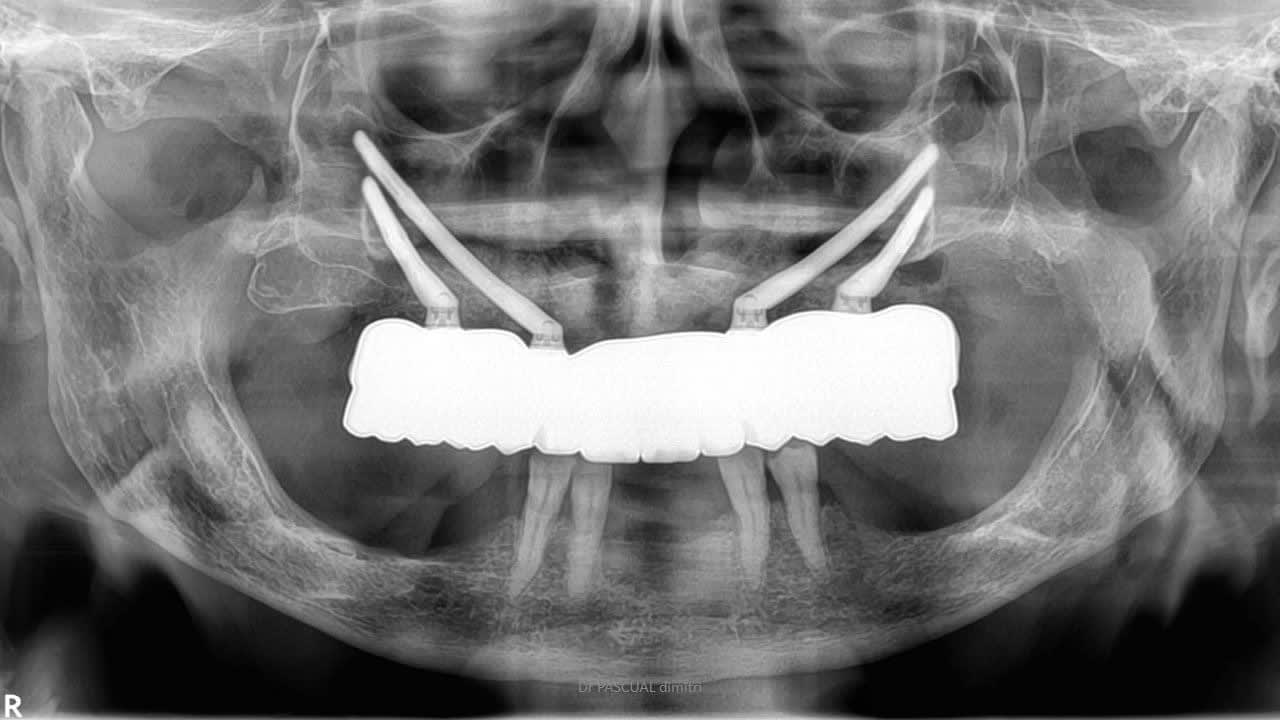

Autres cas de Dimitri : Quad zygo guidé, bridge full zircone tibase collé à l’avance.

Toutes tes interventions sont en fait pour arriver à la conclusion que le mieux , c’est un guide métallique, stérilisable, à appuis osseux , avec une mise en charge immédiate en fin de chir.

Je te montre donc un protocole qui utilise un guide métal , à appuis osseux, avec mise en charge instantanée d’un bridge zircone définitif.

Je crois que la, il n’y a plus de doute . Full zircone avec rosenscrew, pas de tibase .

En effet il n'y a plus de doute, le bridge n'est pas passif. Comme les implants viennent d'être posés et avec l'aide des vis rosenscrew il contraint les implants dans la prothèse. Sur 4 implants cela peut être fait, sur 8 c'est beaucoup moins évident. Si un des implants dévie plus il ne met pas en charge. La question est quel pourcentage de bridge non posé et combien perte d'implants à 5 ans ?

Si j'ai bien compris le principe est de poser seulement 4 implants et un bridge d'usage en zircone pour pouvoir pratiquer des tarifs au plus bas?